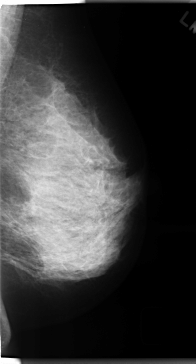

C_0166_1.LEFT_MLO

LEFT_MLO LINES 4720 PIXELS_PER_LINE 2536 BITS_PER_PIXEL 12 RESOLUTION 50 NON_OVERLAY